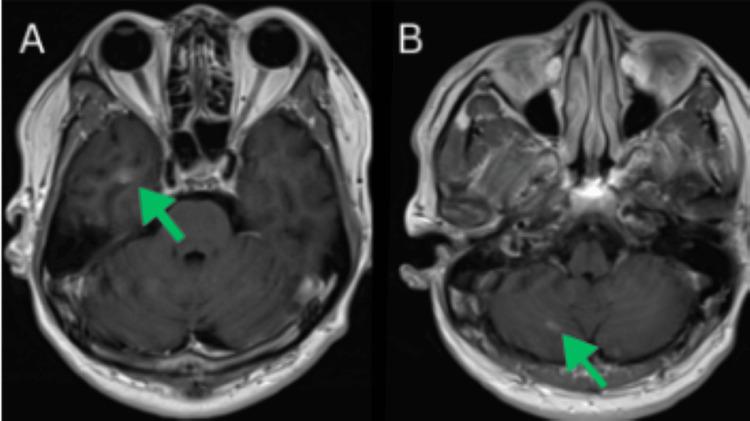

Lung cancer remains the leading cause of cancer-related deaths globally. While smoking-related lung cancers still account for most cases and cause approximately 100,000 deaths annually in the USA, smoking rates have been declining for decades. Lung cancer in never-smokers (LCINS), which tends to affect women and Asian populations, is now the fifth most common cause of cancer-related deaths worldwide. In 2023, over 20,000 lung cancer deaths in the USA were projected to occur in never-smokers, making LCINS the eighth leading cause of cancer-related mortality in the country. As the number of LCINS cases rises, it becomes increasingly important to explore the unique causes and characteristics of the disease, which calls for tailored diagnostic approaches and personalized treatment plans. Lung adenocarcinoma (LUAD) can present with atypical imaging features that often resemble benign conditions, including pneumonia, lung abscesses, post-infectious scarring, atelectasis, mediastinal masses, emphysema, and granulomatous disease. This variability in presentation can hinder accurate diagnosis and potentially delay timely treatment. While lung cancer is uncommon in younger individuals, with only 5.6% of new cases occurring in those under 54 years old, clinicians should maintain a high index of suspicion, as early detection is essential, and atypical cases can be easily missed. Here, we present a complex case involving an unusual radiologic manifestation of a lung mass, in which tuberculosis was initially considered the primary differential diagnosis.

肺癌仍然是全球癌症相关死亡的主要原因。虽然与吸烟相关的肺癌仍然占大多数病例,并且在美国每年导致约10万例死亡,但吸烟率几十年来一直在下降。从不吸烟者中的肺癌(LCINS),往往影响女性和亚洲人群,现在是全球癌症相关死亡的第五大常见原因。2023年,预计美国超过2万例肺癌死亡将发生在从不吸烟者中,使LCINS成为该国癌症相关死亡率的第八大原因。随着LCINS病例数量的增加,探索该疾病的独特病因和特征变得越来越重要,这需要量身定制的诊断方法和个性化的治疗方案。肺腺癌(LUAD)可能表现出非典型的影像学特征,这些特征通常类似于良性疾病,包括肺炎、肺脓肿、感染后瘢痕、肺不张、纵隔肿块、肺气肿和肉芽肿性疾病。这种表现的变异性可能会阻碍准确诊断并可能延迟及时治疗。虽然肺癌在年轻人中并不常见,只有5.6%的新病例发生在54岁以下的人群中,但临床医生应保持高度的怀疑指数,因为早期检测至关重要,非典型病例很容易被漏诊。在此,我们介绍一个复杂病例,涉及肺部肿块的不寻常放射学表现,其中最初将肺结核视为主要鉴别诊断。